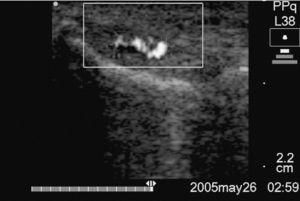

Caso 1. Número de sesiones: 2; satisfacción del paciente: Sí; efectos adversos: No; vasos antes: +3; vasos después: +1; escala escala analógica visual [VAS] antes: 90; escala VAS después: 10; retorno laboral (figs. 2a y b).

Figura 2a Corte longitudinal del tendón del caso 1 previo a la primera esclerosis con neovascularización +3.

Figura 2b Corte longitudinal del tendón de la figura 2a donde, tras 2 sesiones esclerosantes y ejercicios excéntricos, mostró una neovascularización +1.